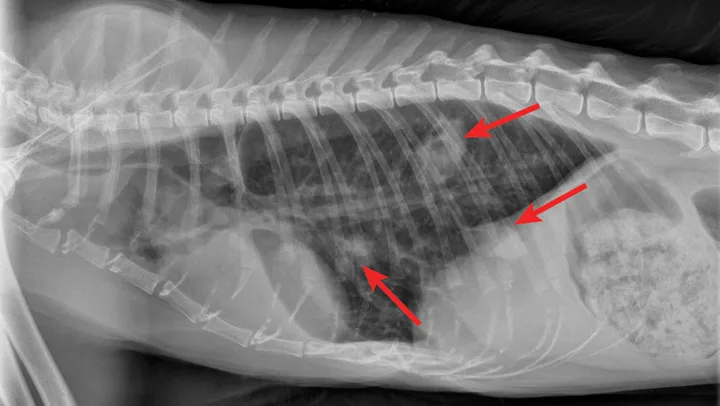

Overt cardiomegaly may be understated on radiographs because of changes in internal diameter that do not affect the overall cardiac silhouette. Vertebral heart score >9.3 supports a CHF diagnosis.1 Pulmonary venous congestion can be absent, and pulmonary arterial distension may be appreciated. The presence of pleural effusion with simultaneous pulmonary infiltrates is supportive of CHF (Figure 1).2

Congestive heart failure. Note the pleural effusion (arrows).